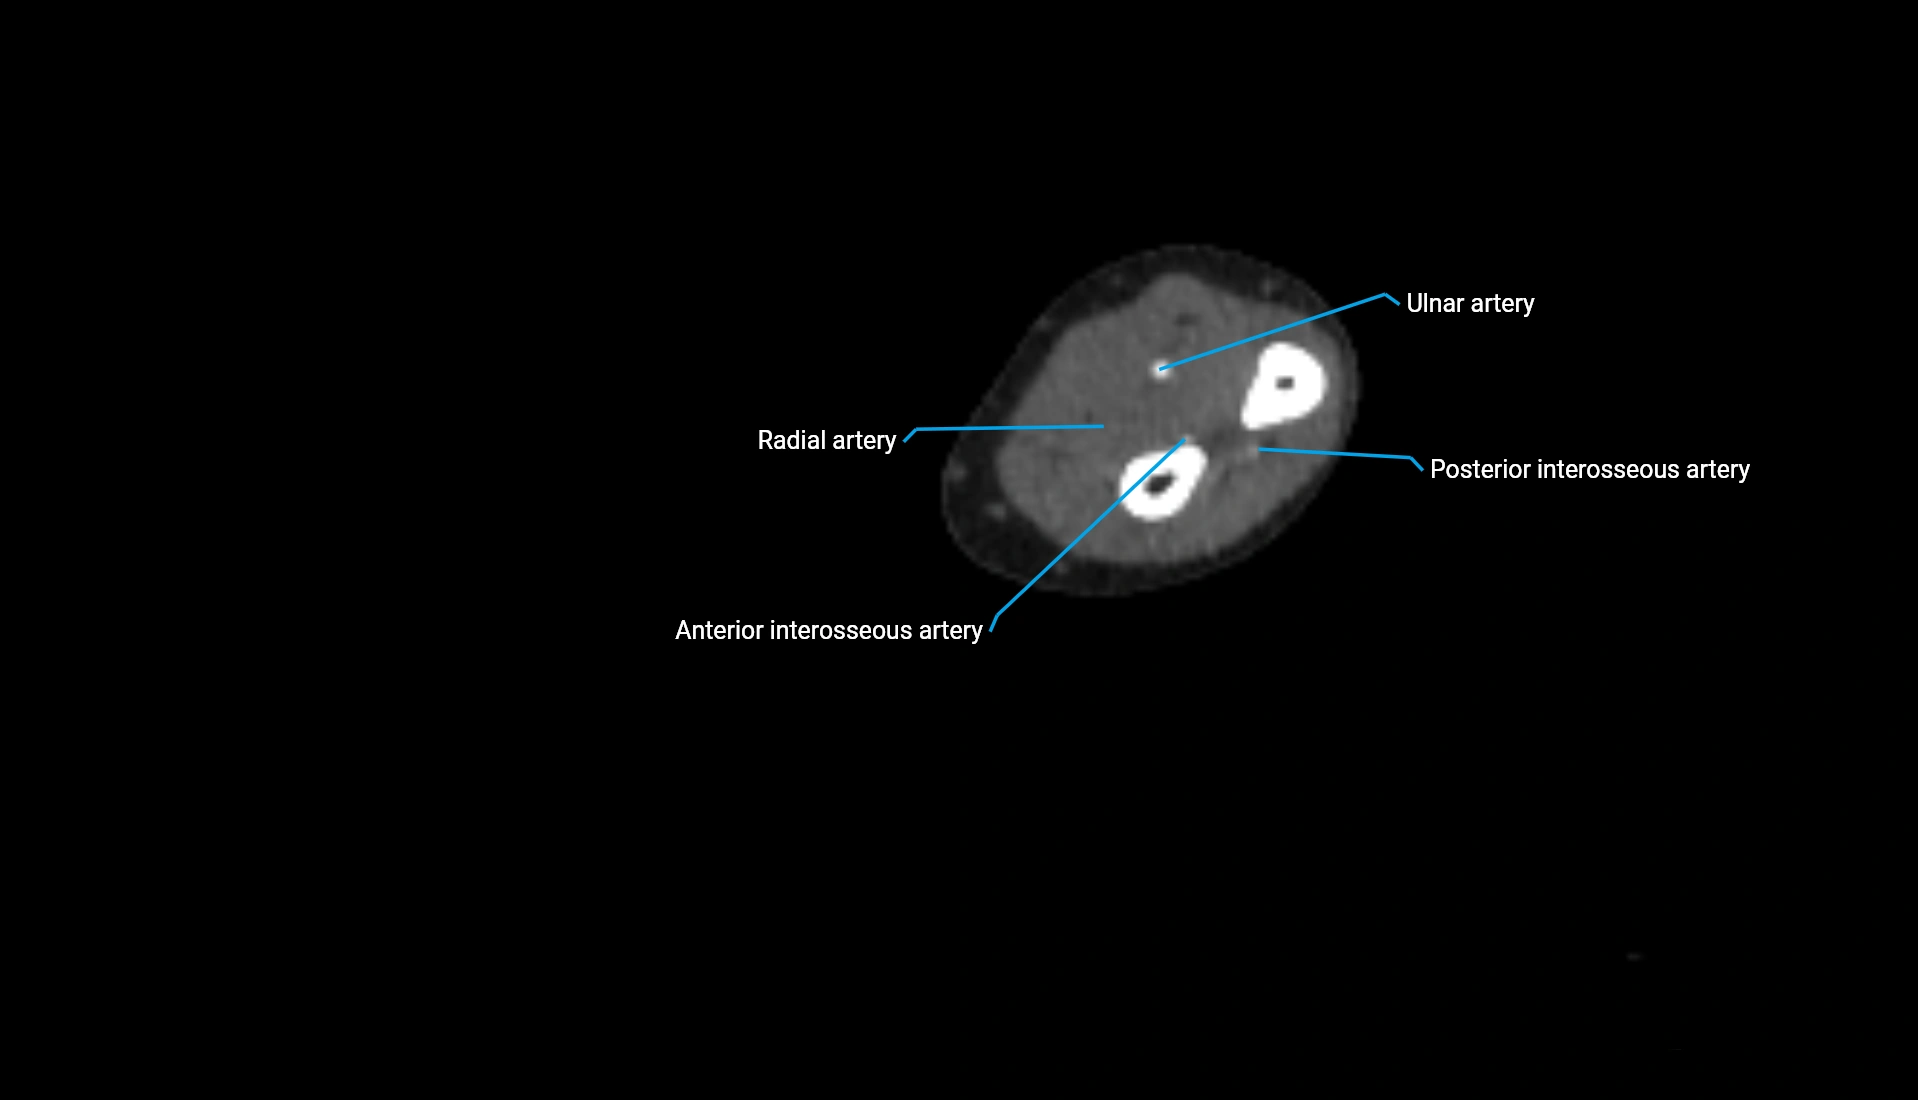

CT Appearance

Non-Contrast CT:

• Cortex: High-density, sharply defined

• Subchondral bone: Dense cancellous matrix

• Articular surface: Smooth concave contour articulating with the capitellum

• Excellent for evaluating bone integrity, alignment, and subtle fractures

Post-Contrast CT:

• Bone: No enhancement

• Joint capsule and synovium: Mild enhancement outlining the joint

• Improves contrast between soft tissues and bony margins

• Useful in detecting subtle joint abnormalities or postoperative changes